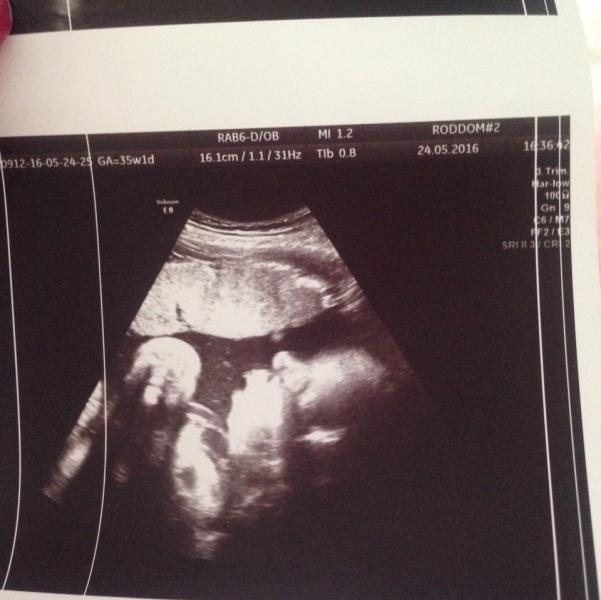

Наша курносая и губастая позировала на УЗИ ☺️😍 немножко осталось до нашей встречи!👑🙏🏻❤️ мы очень ждём тебя 👼🏼

Это УЗИ делали почти в 36 недель весели 2900☺️ сейчас уже больше 3х кг думаю